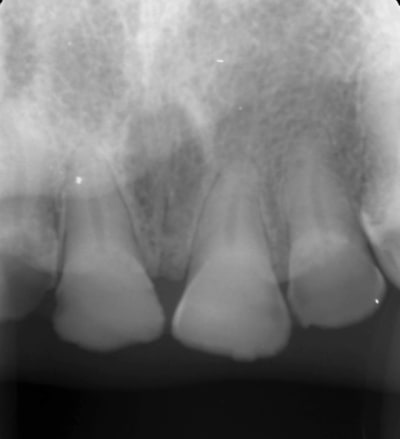

Radio 11

8af24b3d fd05 4021 a759 7a5e9e05a6a7 h5jlk1 - Eugenol